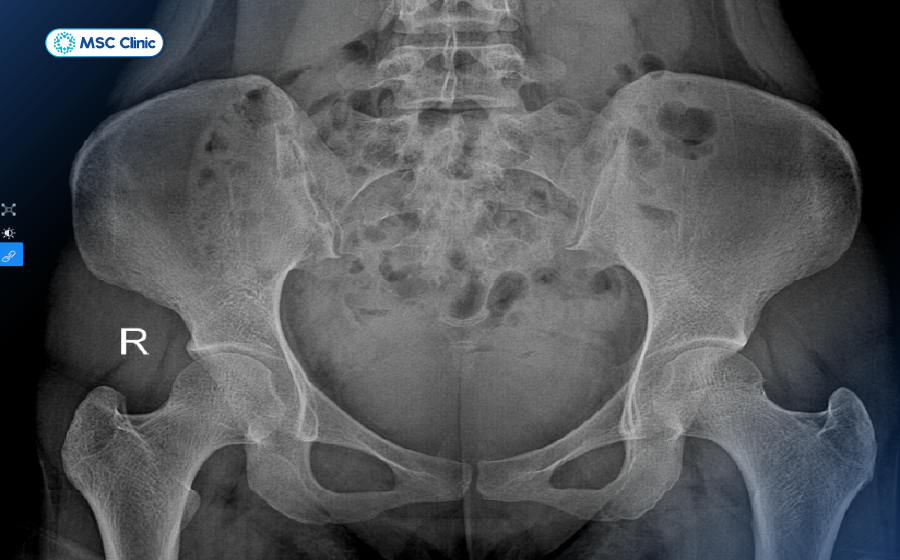

- Chụp X-quang: Loại trừ các vấn đề về xương như trượt đốt sống hoặc gãy xương. Những biến đổi như gai xương hay hẹp khe khớp trên phim chụp là những dấu hiệu quan trọng để định hướng điều trị lâu dài.

Phim X-quang giúp xác định có tình trạng gai xương chèn ép hay không